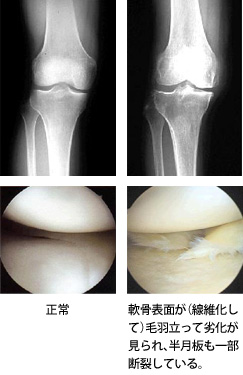

膝関節鏡視下手術に関する書籍。「ビジュアル・サージカルテクニック 膝関節鏡視下手術」石橋恭之、出家正隆定価14300円(税抜13000円+税10%)ご覧いただきありがとうございます。※本商品は裁断済みのため、「全体的に状態が悪い」としております。※新品のまま裁断しましたので書き込みやマーカーはございません。※ 少々のページ折れなどあるかもしれませんが、何卒ご容赦ください。宜しくお願い致します。商品の特性上、返品交換は申し訳ございませんが致しかねますのでご理解宜しくお願い致します。#整形外科#膝関節#膝関節鏡#半月板#前十字靭帯#石橋恭之#出家正隆